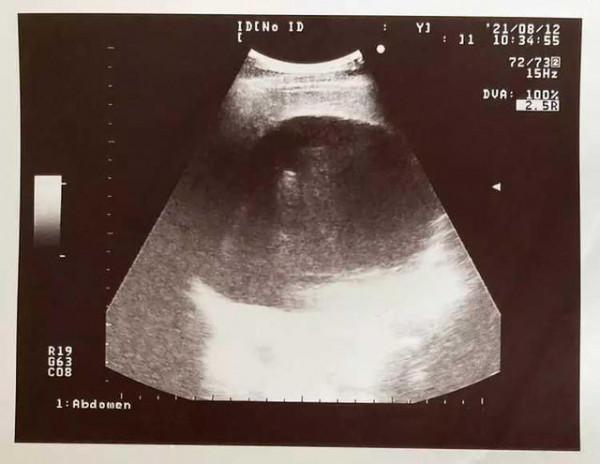

值得一提的是,苦苓的肝臟多年來狀態確實不太好。直到2012年例行身體檢查時,他發現自己的腎臟長了一顆腫瘤。

迫不得已前往醫院診療的他沒過多久便被醫生下了診斷:原來他的肝臟裡,竟然藏著一顆重達14.5公斤的巨型腫瘤,此外身體裡還有超400萬個B肝病毒。